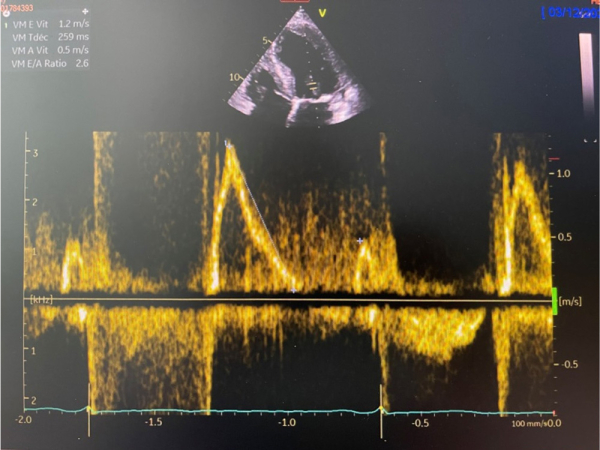

Paramètres échographiques

Figure 1

Figure 2

Figure 3

Figure 4

Figure 5

Figure 6